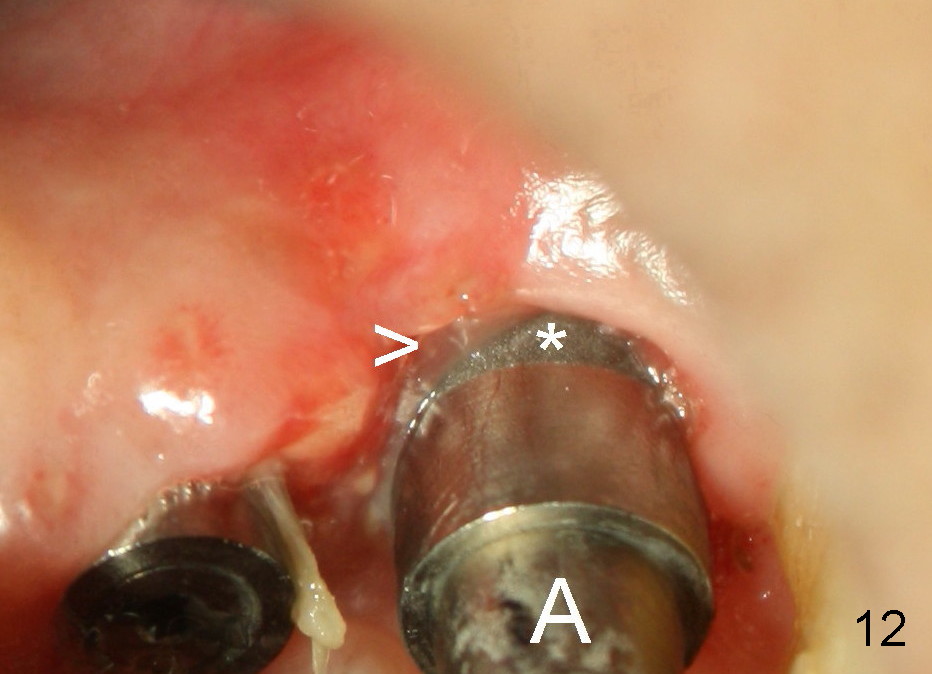

The perio dressing dislodges 18 days postop (Fig.12 magnification). By that time, the extraction wound has healed. The exposed rough surface of the implant (*) is most likely to be covered by fresh and healthy granulation tissue (>) underneath the gingiva. Subsequently the abutment (A) is removed, since it has finished its temporary function.